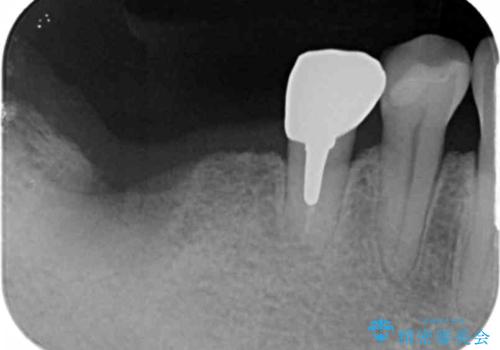

- 77万円(インプラント×2 アバットメント×2 ジルコニアクラウン×2 骨の造成)費用は治療当時の料金となります

今回はインプラント埋入時に固定が得られたので同時に骨の造成を行い治療を進めることができました。